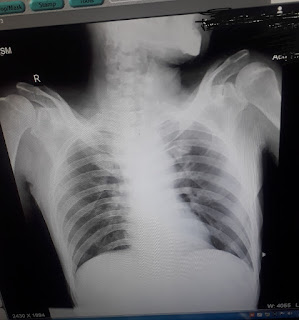

CHEST XRAY